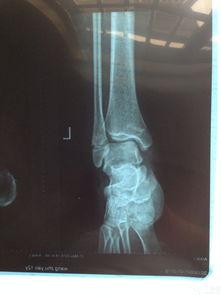

视频接着展示了医生对男子进行诊断的过程。医生首先询问了男子的受伤经过,然后仔细观察了他的小腿。在确认了骨折的位置后,医生用X光片进一步确认了骨折的程度。这一环节让我们看到了医生的专业素养和严谨的工作态度。